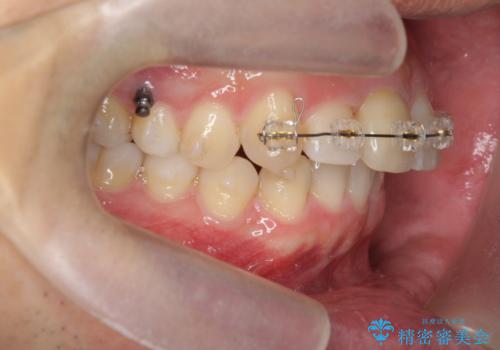

2級ディープバイト 遠心移動を伴うマウスピース矯正

・深い噛み合わせ(ディープバイト) ・2級性の咬合関係(上顎前突)・前歯のがたつき

以上のような歯並びの問題をマウスピース矯正インビザライン・カリエール・マイクロインプラント・部分ワイヤー矯正

を用いて改善していきます。

深い噛み合わせと上顎前突の状態を治すのに時間がかかりましたが、治療後は理想的で安定した咬合関係となりました。